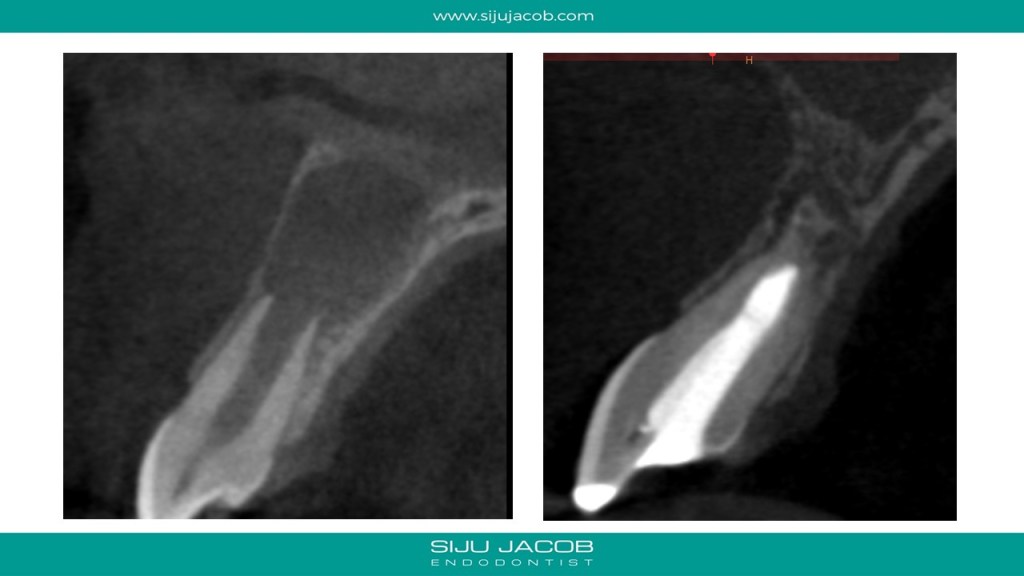

This was probably the largest lesion I ever treated. It had several interesting characteristics. It would be tough to explain with just pics. So, I made it into a short presentation